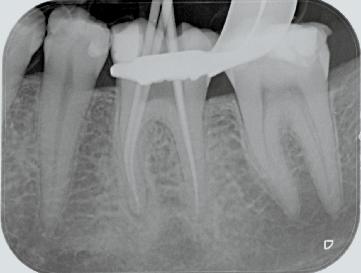

FQ . Clinical Case.

Dr. David Christofzik Specialist for endodontics and traumatology, Kiel /Germany

Rafael Michiels

for endodontics

“FQ allows general practitioners to proceed with a great deal more security and confidence, whereas the high versatility of the instruments enables specialists to respond individually to complicated canal anatomies, as shown in the patient case.”